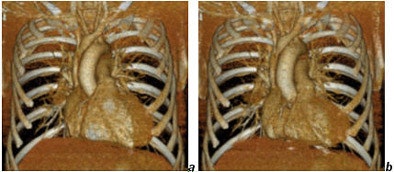

![]() |

| Cardiac images reconstructed from a gated chest CT obtained with a collimation of 40 x 0.625 mm and a dose of CTDIvol = 20 mGy. Reconstructions (a) in diastole, (b) in systole. Images courtesy of Dr. Mathias Prokop. |